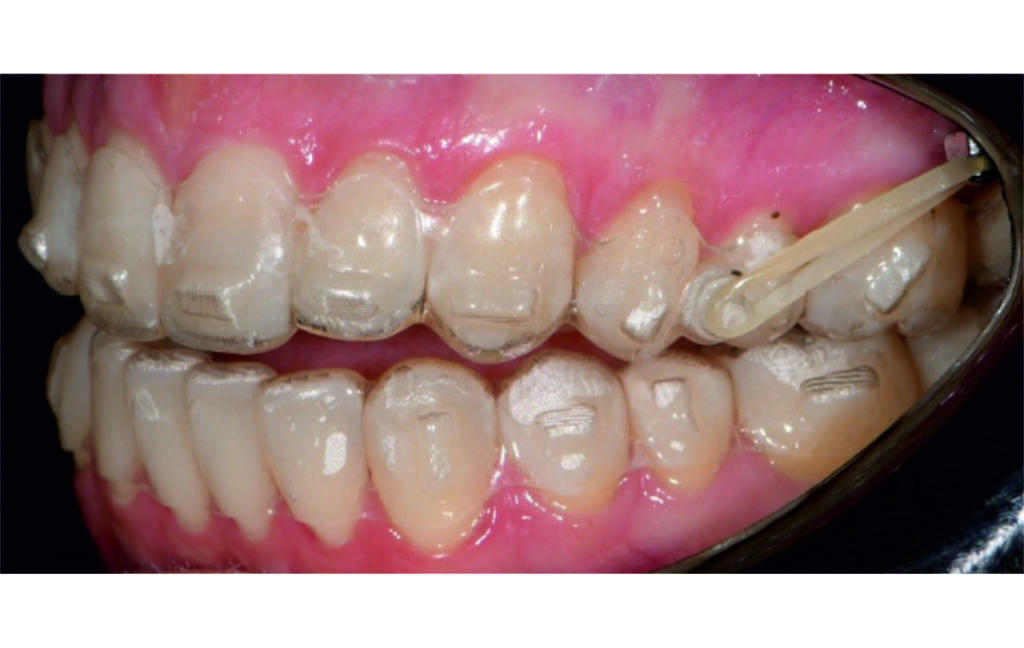

Vertical vector of elastic traction on buttons and IZC helped with the open bite correction.

No sequential distalization for Class II tendency correction was performed due to skeletal anchorage. Lingual attachments were used to improve aligner grip and control tooth movement, as small, angulated lower incisors are difficult to move due to limited anatomy.

An infrazygomatic crest (IZC) screw with force applied between the upper premolars produces a clockwise rotation of the maxillary occlusal plane. This movement aids in closing the anterior open bite and improves upper incisor display. IZC screws with elastics also enable planned intrusion of the upper molars by 1 mm. Because mandibular derotation after upper posterior correction is difficult to predict, anterior distalization and midline correction were performed in the later stages of treatment.